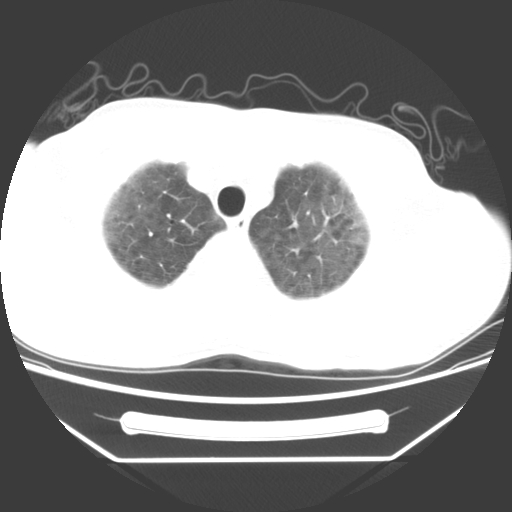

病人55岁,咳嗽,胸闷

忘了传病史了,病人55岁,咳嗽,胸闷

病人是否发烧,两肺“磨玻璃”影,其间见空气支气管征和碎路石征。考虑肺泡蛋白沉着症。

两肺广泛对称磨玻璃样影,密度不均,考虑机遇性肺部感染。

双肺弥漫磨玻璃样病变,病史很重要。有感冒或发烧史,甲流不除外。无发烧可考虑肺泡蛋白沉积,但肺泡蛋白沉积边缘往往较清晰,与正常肺组织分界清晰

两肺弥漫间质性病变,考虑肺泡蛋白沉着症。建议进一步检查。

两肺“磨玻璃”影,其间见空气支气管征和碎路石征。考虑肺泡蛋白沉着症。